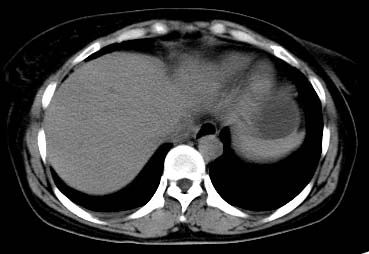

以下是引用西北一只狼在2008-6-30 20:58:00的发言:[br]肝左叶胆管细胞ca并肝门淋巴结转移、胰腺、胃小弯浸润

以下是引用ydx_74在2008-6-30 21:54:00的发言:[br]左叶胆管细胞ca并肝门淋巴结转移、胰腺、胃小弯浸润